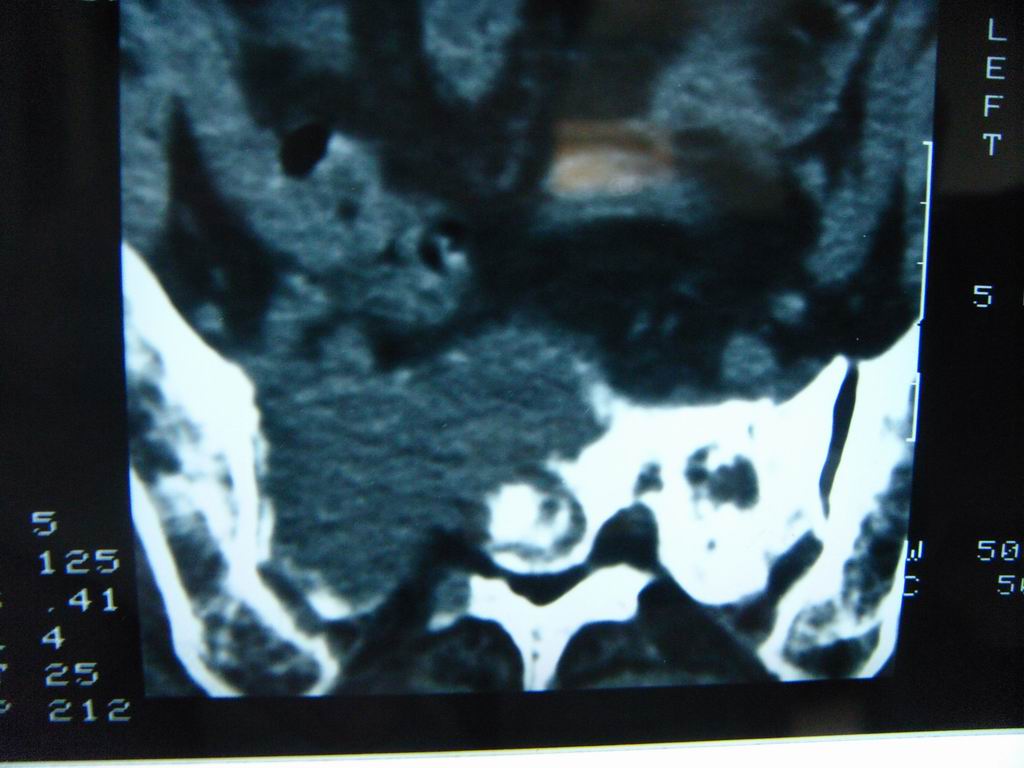

标题: CT21430:女性65岁 乳腺癌术后3年 [打印本页]

标题: CT21430:女性65岁 乳腺癌术后3年

结合病史,考虑骶骨转移瘤,但软组织肿块未突破骨壳,骨巨细胞瘤不能完全排除,骨髓瘤及脊索瘤不考虑。

结合病史,考虑骶骨转移瘤。

结合病史,考虑骶骨转移瘤。其它椎体,如腰5是否有问题呢?

个人感觉骨巨细胞瘤可能性大些。